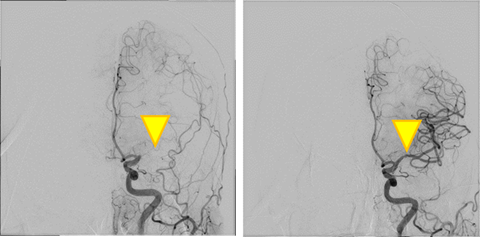

脳血管疾患では脳動脈瘤や短絡疾患に対する塞栓術や、脳梗塞に対する血栓回収療法、頚動脈狭窄症に対する頚動脈ステント留置術などの治療を行っています。短絡疾患では動脈と静脈が複雑に絡み合っているため治療血管を把握することが容易ではありません。そこで高精細な血管の3D画像を血管ごとに色分けして提供することで、医師が治療戦略を考える際の手助けとなり、術中の手技時間の短縮や被ばく低減などにもつながっています。

脳梗塞に対する血栓回収療法(治療前・治療後)